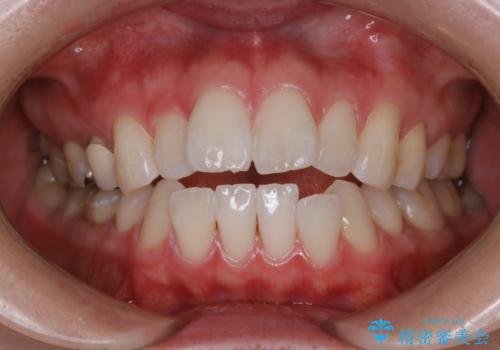

初めてのホワイトニングで自然に白く

- 歯科医院では初めてのホワイトニングとのことでした。

処置前クリーニングとスペシャルコースを行いました。

- ¥15730費用は治療当時の料金となります